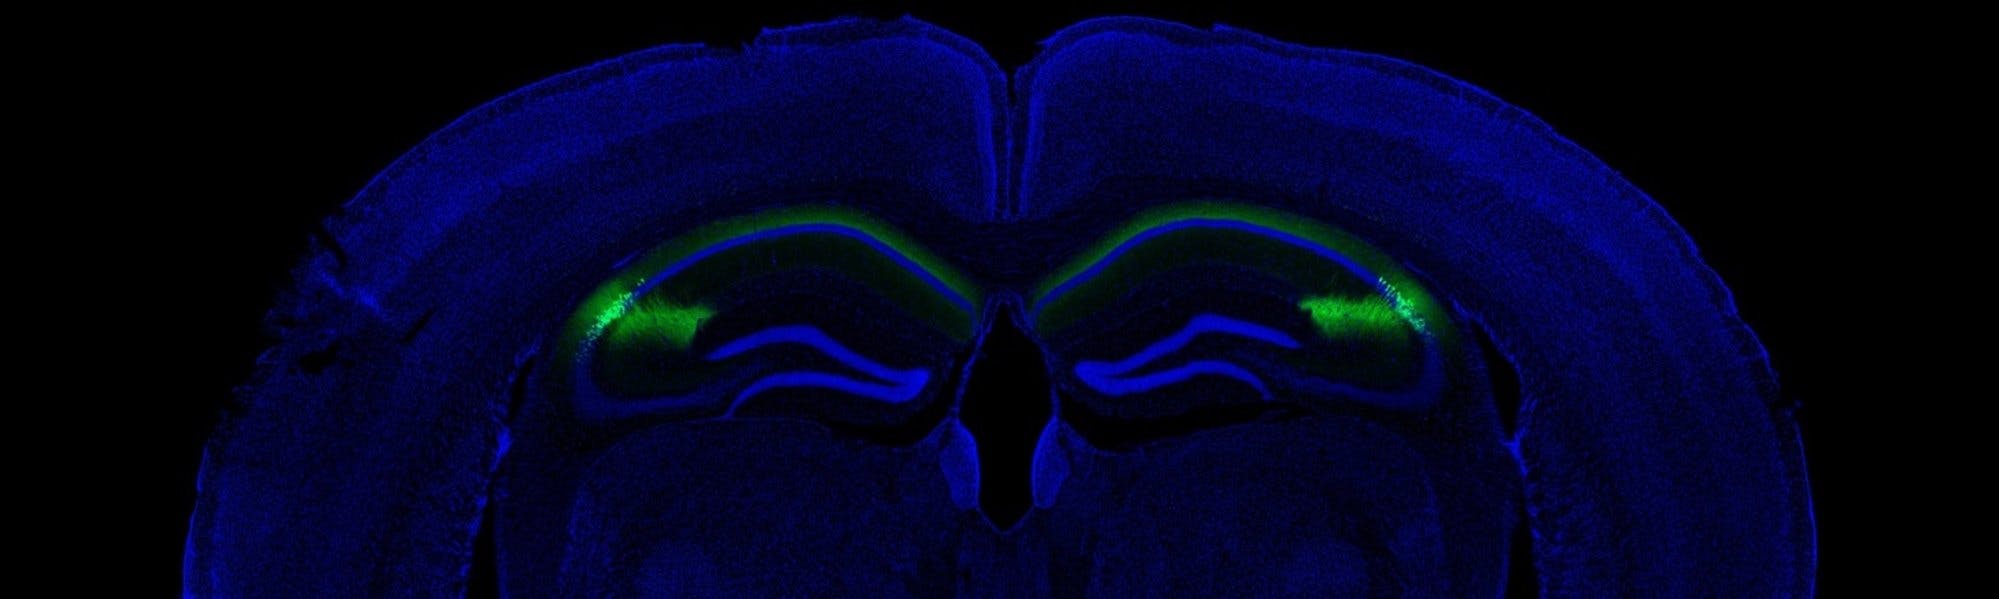

Psychiatric disorders related to integrity of hippocampal area CA2

A mouse model of 22q11.2 deletion syndrome shows unique alterations in area CA2 of the hippocampus and social memory deficits. The results of a study from Paris Descartes and Columbia Universities shows this region of the brain may play a significant role in some psychiatric and neurodevelopmental disorders. This pharmacologically unexplored area could be a potential therapeutic target for psychiatric diseases.

22q11.2 deletion syndrome affects an estimated 1 in 4,000 people and is a genetic risk factor for several neuropsychiatric disorders, including schizophrenia. The transatlantic collaborators, who recently published a paper on their findings in Neuron, used the Df(16)A+/- mouse model of the syndrome to examine how area CA2 is altered in psychiatric illness. Numerous post-mortem studies of schizophrenic and psychotic patients have shown that the CA2 region undergoes disease-related changes in size and composition, but the local cellular changes in the hippocampal microcircuit are unknown.

Banner image credit: Columbia University Medical Center